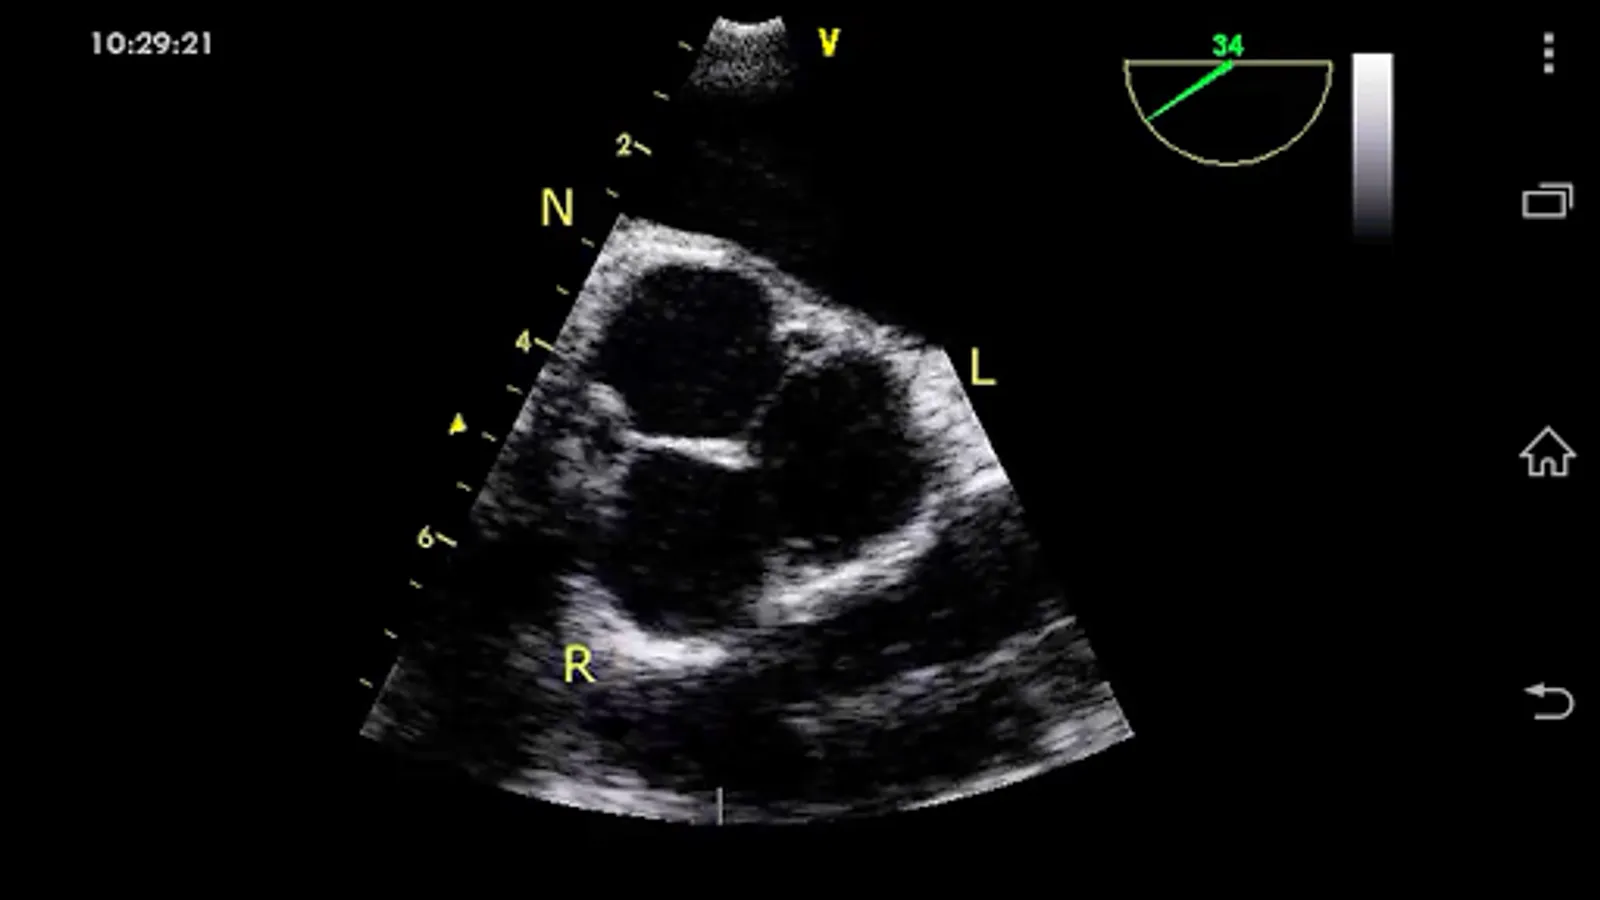

CARDIO3® Comprehensive Atlas of Echocardiography (ISBN 80-969114-8-1) - reference/learning tool for cardiologists, cardiac surgeons, internists, other physicians, and sonographers evaluating echocardiograms for ultrasound diagnosis.